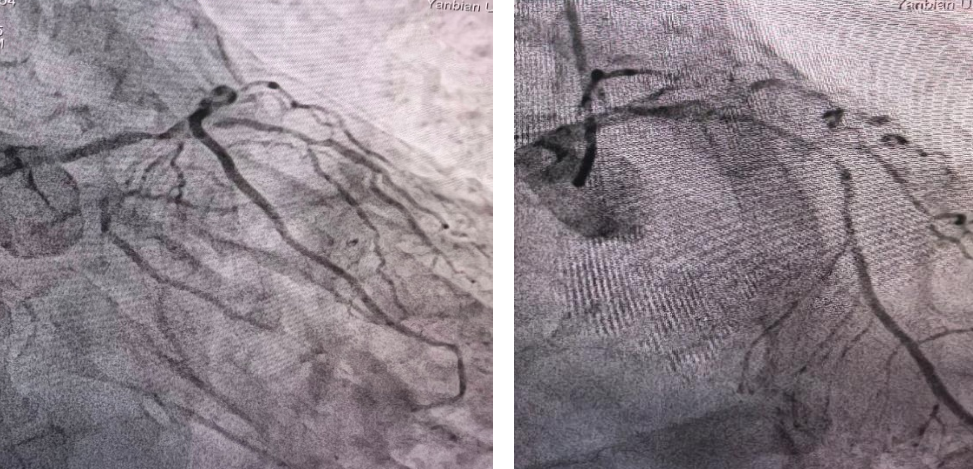

术前造影图像

术后造影图像